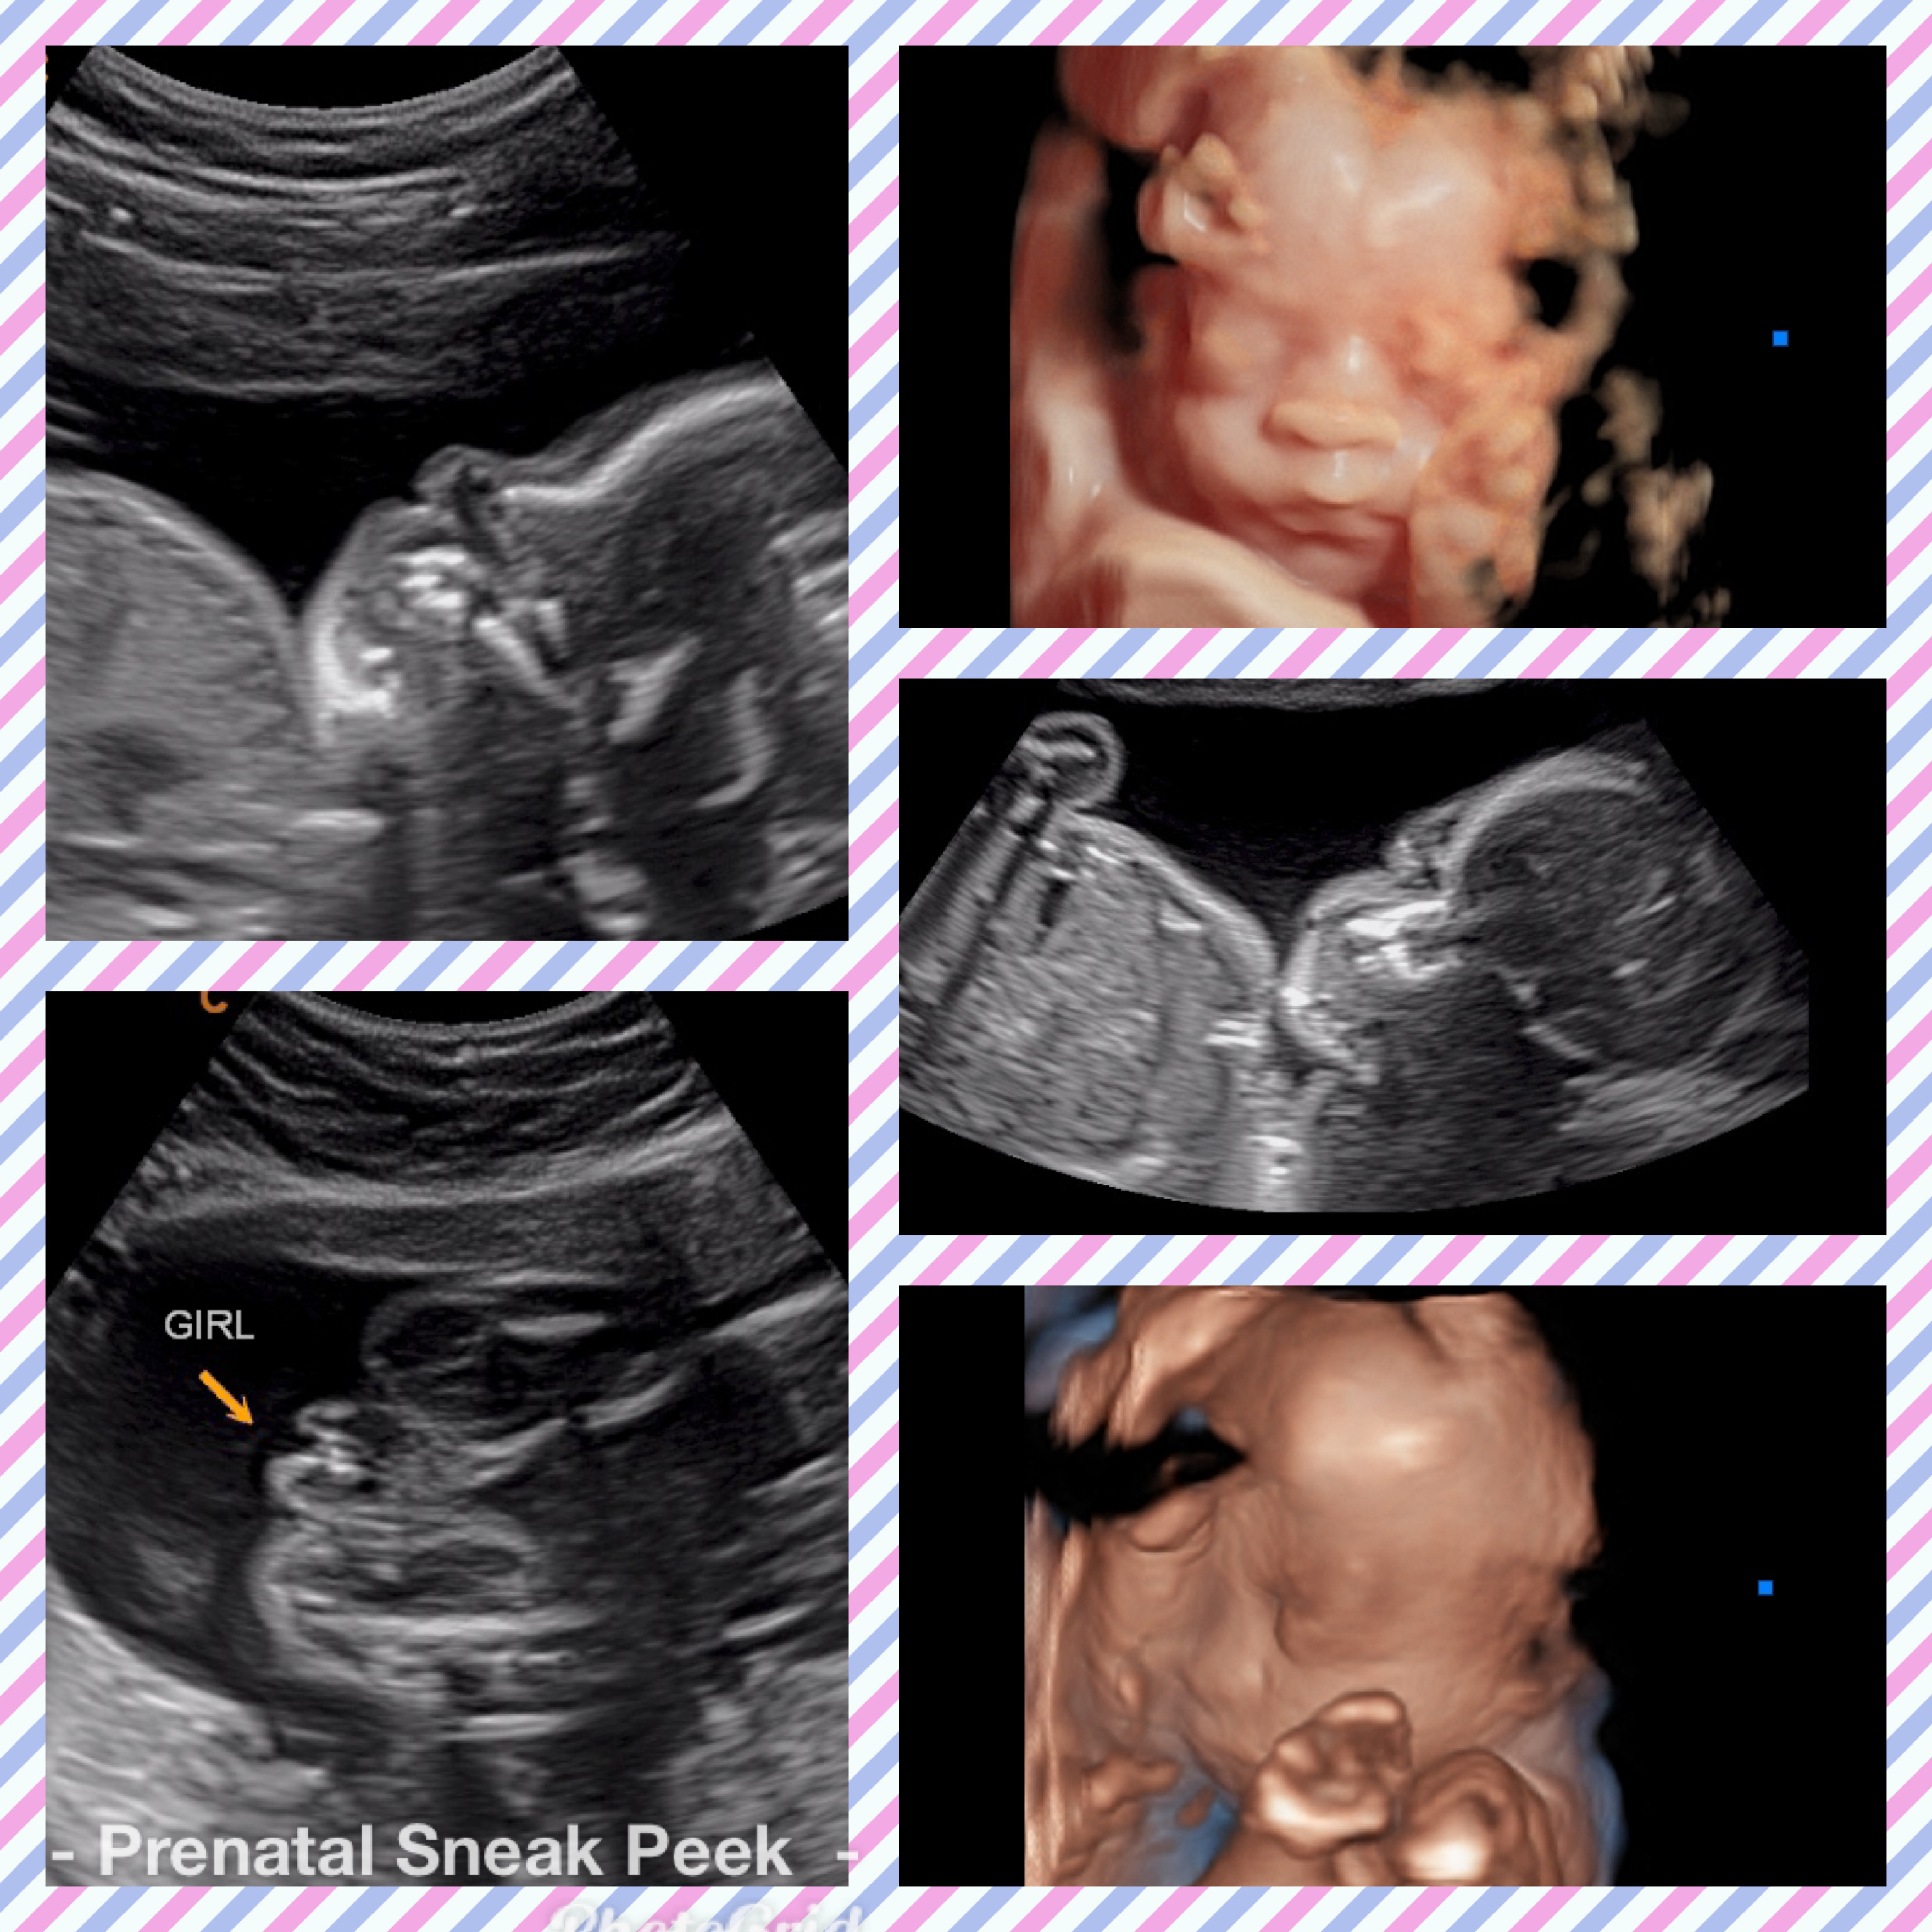

ABOUT PRENATAL SNEAK PEEK

Prenatal Sneak Peek is an elective mobile ultrasound company that provides ultrasounds in the comfort of your home. It is owned and operated out of Bel Air MD. Owner, Kelly Wargo, RDMS is a Registered Diagnostic Medical Sonographer with a specialty certification in OB. She has over 15 yrs. experience in the field of ultrasound. Kelly is the sole operator of her business; therefore, you will get the same quality every time! She also has a heart for saving babies, providing ultrasound services part-time to Options@328 a nonprofit located in Baltimore City.